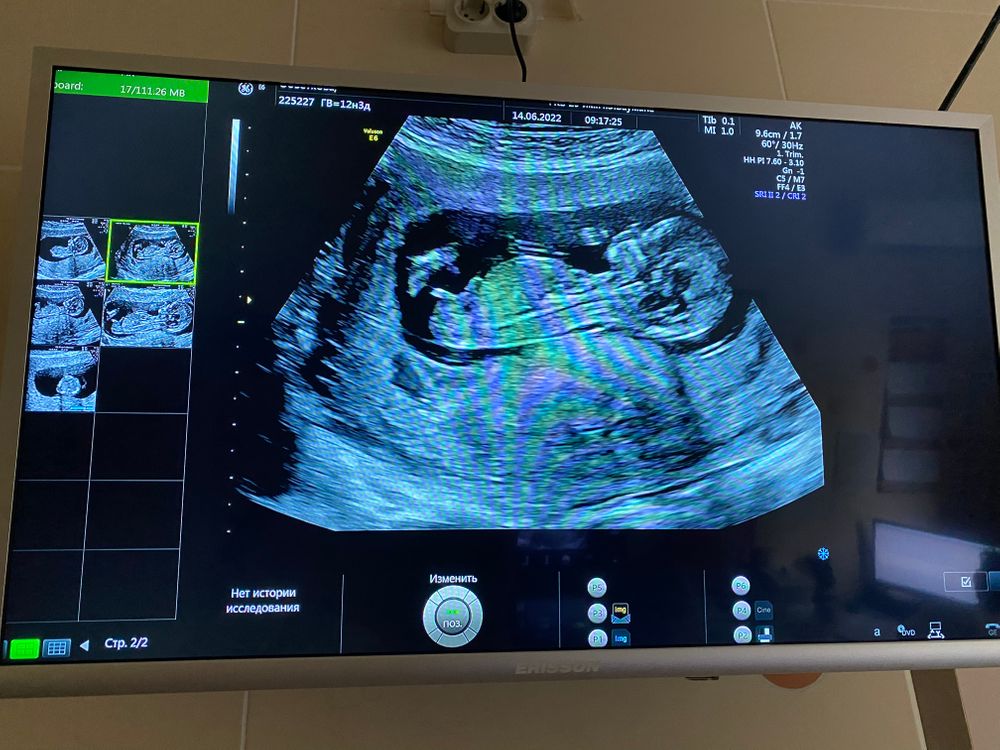

Всем приветик! Прошла я сегодня скрининг и хоть успокоилась😄а то с 8 недель не была на узи и было как то волнительно как там поживает малыш! По узи все соответствует сроку, твп 1.7, носовая кость определяется! Пол не сказала, смотрела смотрела и говорит не буду предполагать) говорит приходите через пару недель и точно скажу! Но я буду ждать 2 скрининг, который будет только 3 августа) односрочницы как вы себя чувствуете?)💐